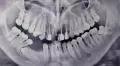

Мне 18 лет. Две недели назад заметила, что вверху за правым клыком растет зуб. Была в ужасе, ведь все зубы молочные у меня выпали. Сделала панорамный снимок, посоветовали вытягивать ретинированный зуб. Но врачи не смогли определиться какой зуб - молочный клык или резец.

Возможно ли вытянуть клык, который стоит напротив резца и расположен на расстоянии более 1 см от своего места в зубном ряду?

По снимку данный зуб - постоянный клык.